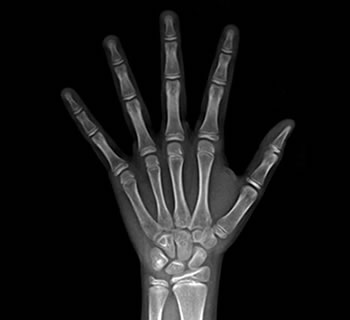

Radiografias Carpais

A radiografia carpal dentro da odontologia vem sendo utilizada principalmente para determinação da idade fisiológica e sua correlação com a cronologia dentária.